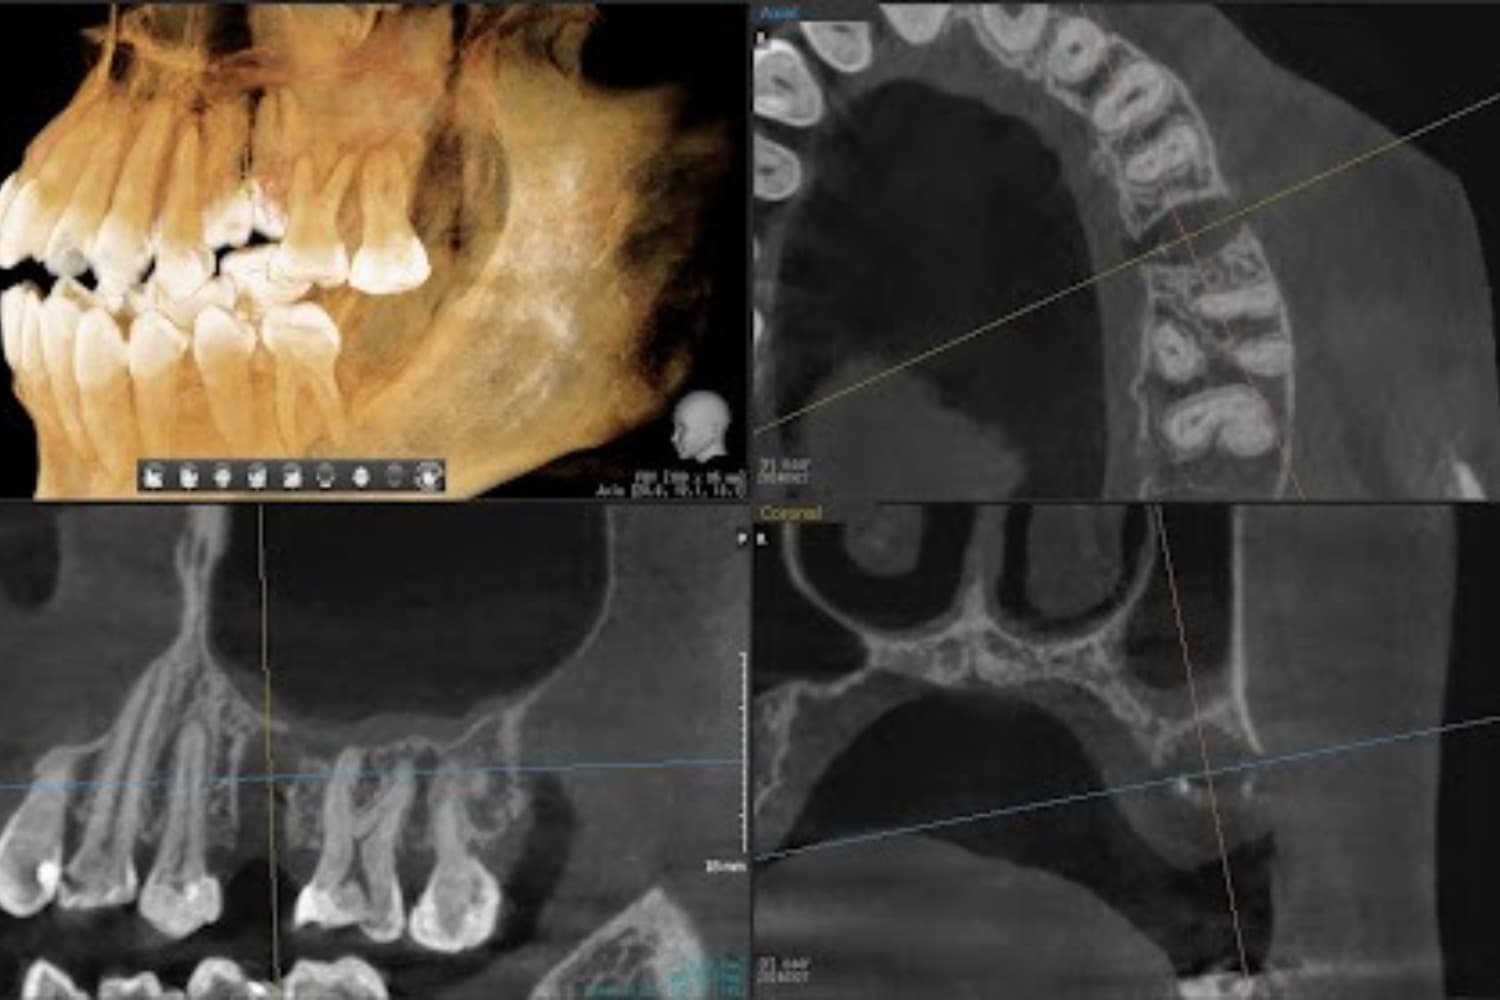

右上の折れた歯のインプラント治療(40代女性)

Before

After

右上の歯が折れて保存することが不可能な状態だったためめ、インプラント抜歯即時埋入をおこなう

年齢

40代

性別

女性

主訴

歯が折れたことを主訴に来院。インプラント治療を希望される。

治療期間

2ヵ月

治療回数

4回

費用

352,000円(税込) 費用の内訳: 【インプラント基本料】330000円(税込み) 基本料金に以下を含む ・フィックスチャー及び手術費用 ・投薬費用、 ・レントゲン費用 ・インプラント上部費用(アバットメントおよびジルコニアクラウンの費用用) 【オプション費用】 ・抜歯即時埋入加算(人工骨費用を含む) 22000円(税込み)

副作用・リスク

・手術後に痛み・腫れ・出血・合併症等を引き起こす恐れがあります。 ・噛む感覚がご自身の歯と異なることがあります。 ・見た目がご自身の歯と異なる場合があります。 ・手術後もメインテナンスを続けないと、インプラントが抜け落ちてしまう恐れがあります。